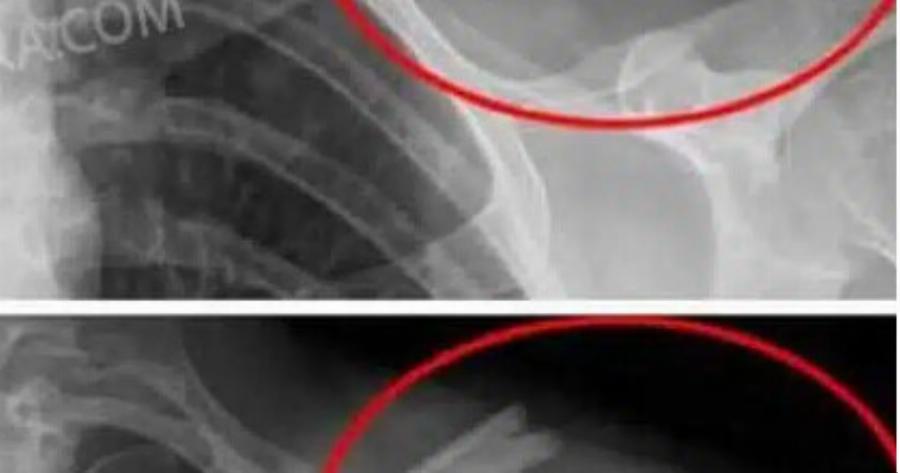

Αποδυναμώνουν τα οστά: Η υψηλή πρόσληψη νατρίου που περιέχουν πολλά από αυτά , μειώνει το ασβέστιο, αυξάνοντας τον κίνδυνο οστεοπόρωσης.